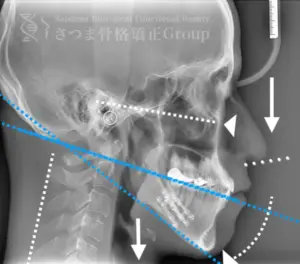

口蓋骨の下方変位 下顎位の滑落 ストレートネック 中顔面と人中が伸びて見える

Inferior displacement of the palatine bone Sagging of the mandibular position Straight neck The midface and philtrum appear elongated

AFTER

口蓋骨を上方に整復 下顎位が上がる ストレートネックの改善 中顔面と人中が短縮し小顔に見える

Repositioning the palatine bone upward The mandibular position is elevated Improvement of straight neck The midface and philtrum are shortened, giving the appearance of a smaller face